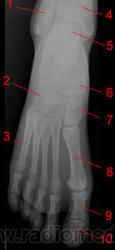

Стопа.

1, Малоберцовая кость.

2, Кубовидная кость.

3, Пятая плюсневая кость.

4, Берцовая кость.

5, Таранная кость.

6, Ладьевидная кость.

7, Cuneiform

8, Первая плюсневая кость

9, Проксимальная фаланга

10, Дистальная фаланга